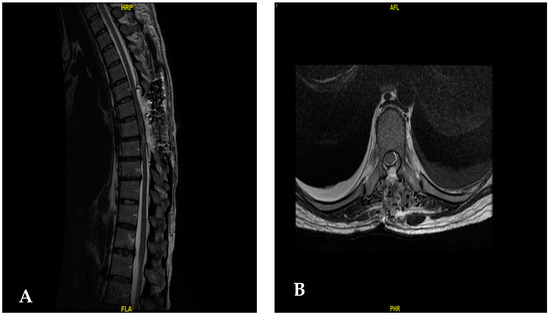

| [30] | 55/Female | T6–T8 | 2-year progressive back pain Weakness on both legs | T6–T8 laminectomy | Angiomatous meningioma | Improvement of motor weakness |